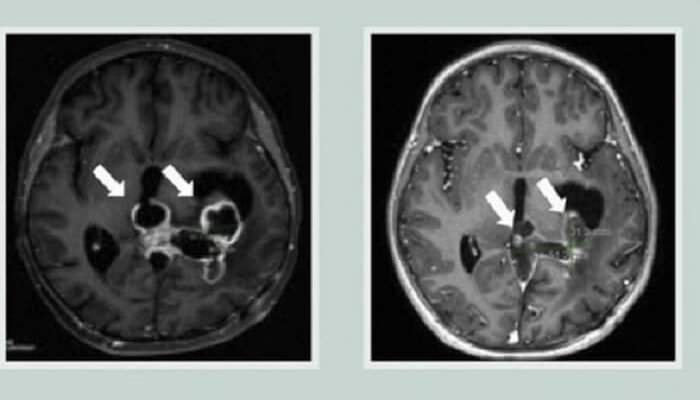

Cercetătorii au dezvoltat un model bazat pe inteligenţă artificială care, în 10 secunde, poate determina, în timpul unei intervenţii chirurgicale, dacă a mai rămas vreo parte a unei tumori cerebrale canceroase care ar putea fi îndepărtată, sugerează un studiu publicat în revista Nature, scrie news.ro.

În acest studiu internaţional al tehnologiei bazate pe inteligenţă artificială, FastGlioma a detectat şi a calculat cantitatea de tumoră rămasă cu o precizie medie de aproximativ 92%, ceea ce face din această tehnologie un instrument accesibil şi la preţuri convenabile pentru echipele neurochirurgicale care operează glioame.